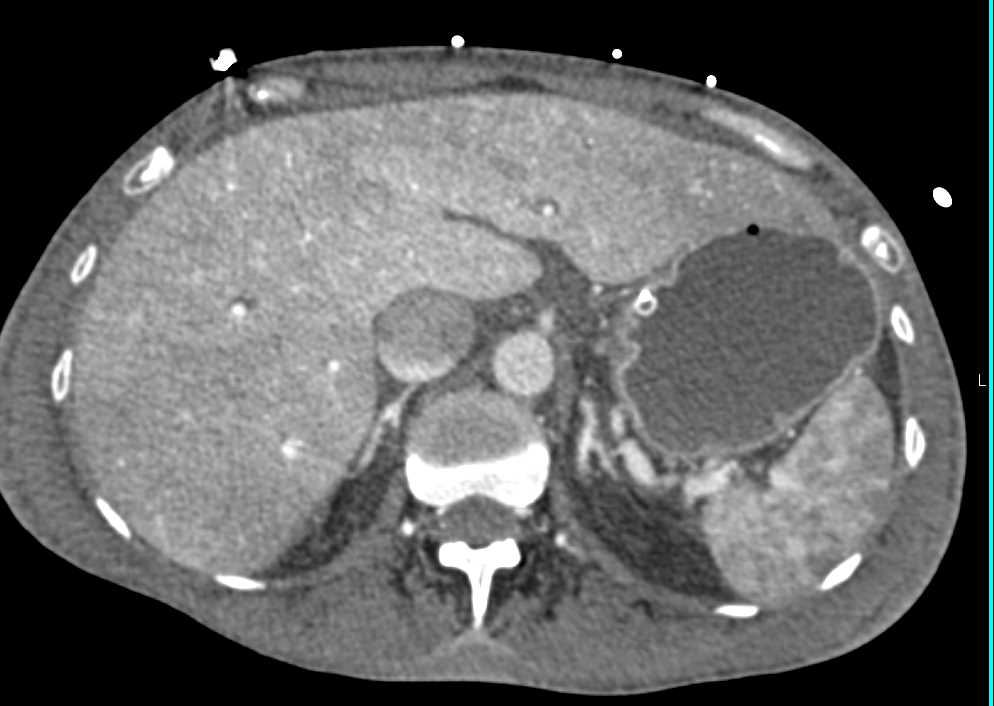

Recurrent Renal Cell Carcinoma Metastatic to the Pancreas, Contralateral Kidney and Adrenal and Adenopathy